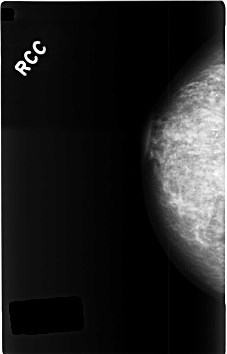

C_0344_1.RIGHT_CC

RIGHT_CC LINES 4600 PIXELS_PER_LINE 2944 BITS_PER_PIXEL 12 RESOLUTION 50 NON_OVERLAY